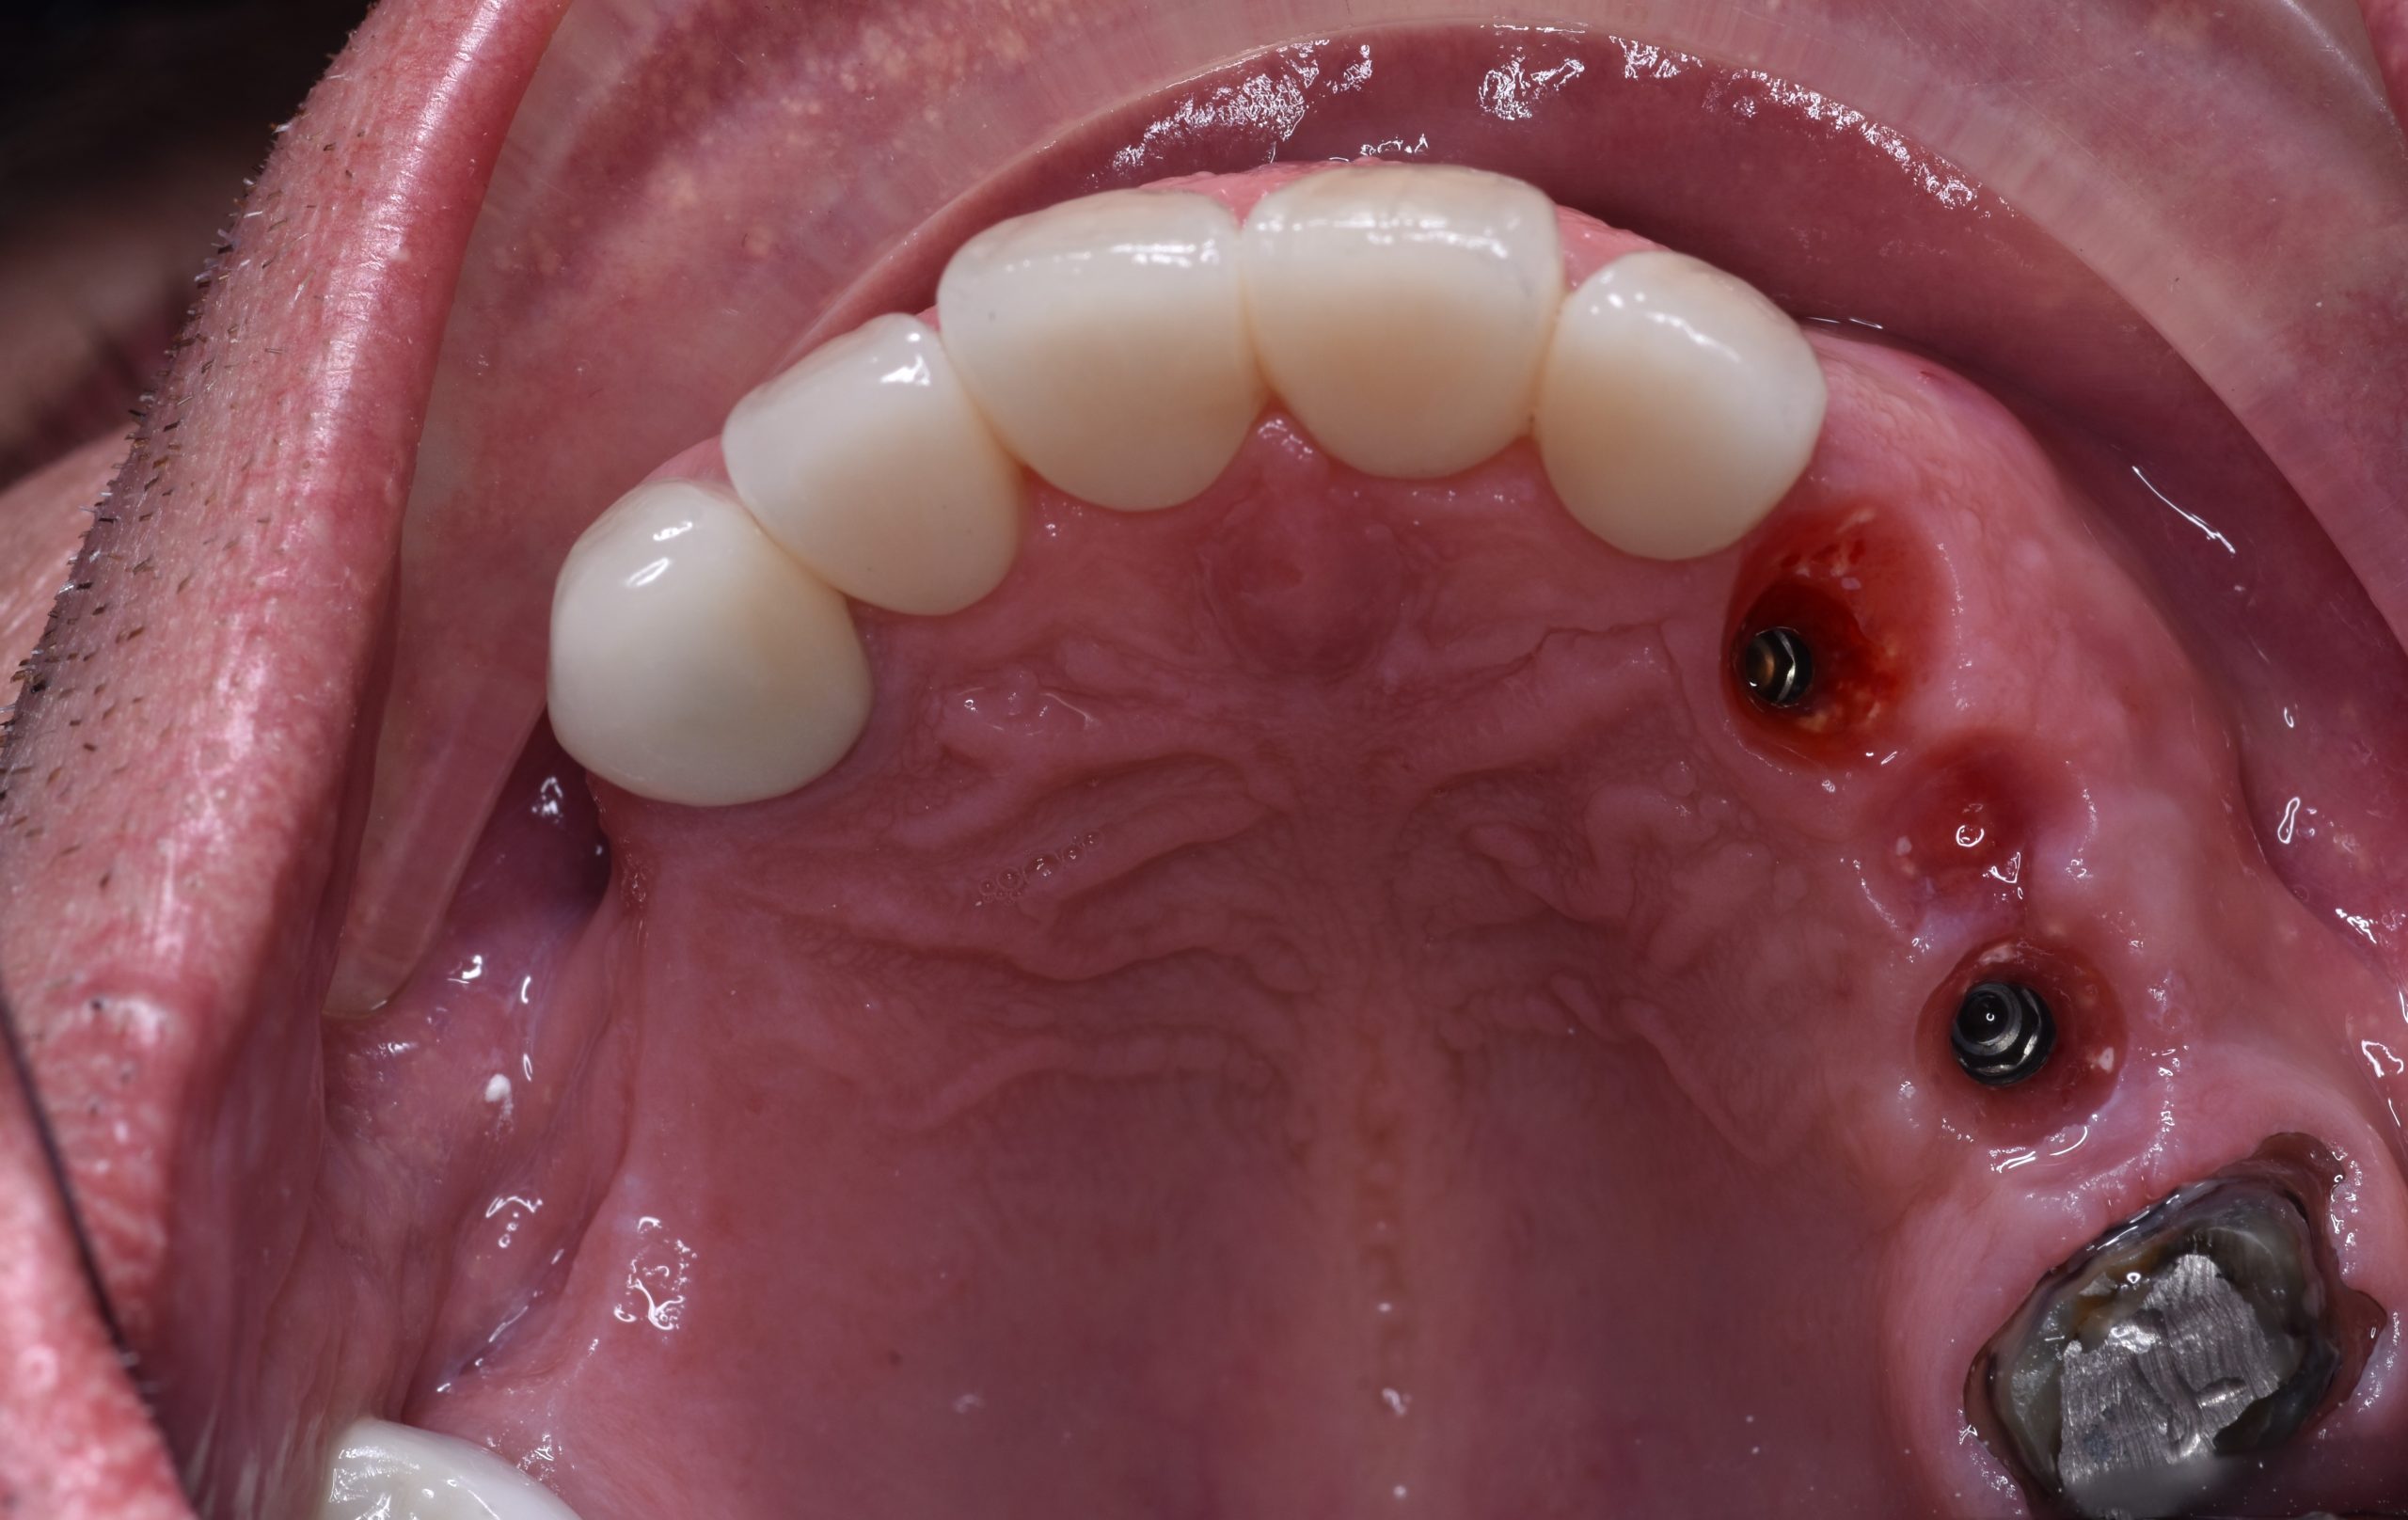

Giai đoạn 4: phục hồi toàn miệng, bao gồm nâng khớp cắn

Thử răng tạm nâng khớp cắn